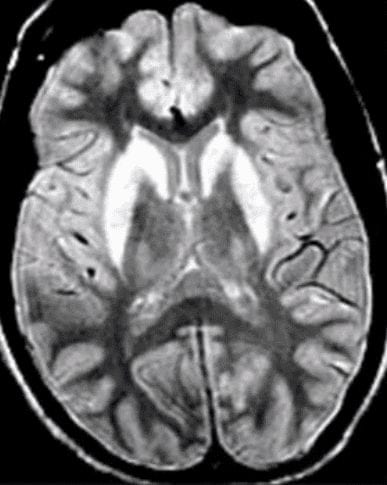

Identify the abnormality and associated disease

Bilateral caudate atrophy. Classic for Huntington's Disease.